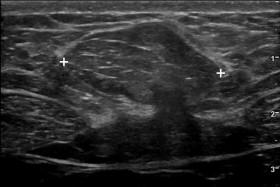

The most common extrauterine/extraovarian site for endometriosis is the abdominal wall, occurring most often in the scars following cesarean sections. Scar endometriomas may be entirely solid or have cystic elements. The margins can be well-defined, lobulated, or infiltrative. Blood flow may or may not be detected ( Fig. 9-32 ). It is important to realize that scar endometriomas do not have the characteristic diffuse, homogeneous, low-level echoes seen with pelvic endometriomas. Given a lack of characteristic sonographic features for abdominal wall endometriomas, a high index of suspicion should exist whenever a lower abdominal wall mass is encountered in a woman. Ultrasound-guided biopsies are usually diagnostic.

F igure 9-32, Abdominal wall endometriomas in different patients. A, Longitudinal color Doppler view shows a solid, hypoechoic mass (cursors) with no detectable vascularity. B, Transverse color Doppler view shows a solid, hypoechoic mass (cursors) with readily detectable vascularity. C, Gray-scale view shows a large, lobulated, heterogeneous mass (cursors). D, Gray-scale view shows a solid and cystic mass (cursors) with infiltrative margins. Needle biopsies confirmed endometriosis in all of these patients.